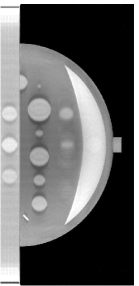

II Breast Phantom

A breast phantom was designed to provide a basis for algorithm comparison. It consists of objects with different geometric shapes to allow for analytic computation of the projection data. The overall shape of the compressed breast of 50 mm thickness is modeled by a truncated ellipsoid. Attenuation coefficients at a photon energy of 30 keV [10] were used for phantom materials simulating the fibroglandular, tumour and muscle tissues, as well as microcalcifications in the breast. In Fig. 1, we display the phantom images within 2D planes specified by (a) mm, by (b) mm, (c) mm, and (d) mm, respectively. As shown in Fig. 1a, the crescent-shaped region, representing the fibroglandular tissue region of the breast, is attached to a rectangular slab of higher attenuation, simulating the pectoralis muscle. It can be observed in Fig. 1 that numerous test objects of different sizes and contrast levels are embedded in the phantom for simulating mass lesions and microcalcifications. In particular, a row of three ellipsoids is embedded in the pectoralis muscle (see Fig. 1(b)), with equal in-plane diameters but varying flatness, thus allowing one to evaluate whether shapes of equal in-plane profile, but different in-depth profiles, can be resolved. Furthermore, six spheres of different diameters, ranging from 5 mm to 15 mm, are equally distributed in the fatty area of the breast (see Fig. 1(c)). It can also be observed in Fig. 1(d) that three pairs of stacked spheres of identical diameter mm are embedded in the breast region with different spacings of , , and , respectively, for these pairs. Finally, two clusters of small spheres of diameters 0.3 mm and 0.15 mm are included to model microcalcifications.